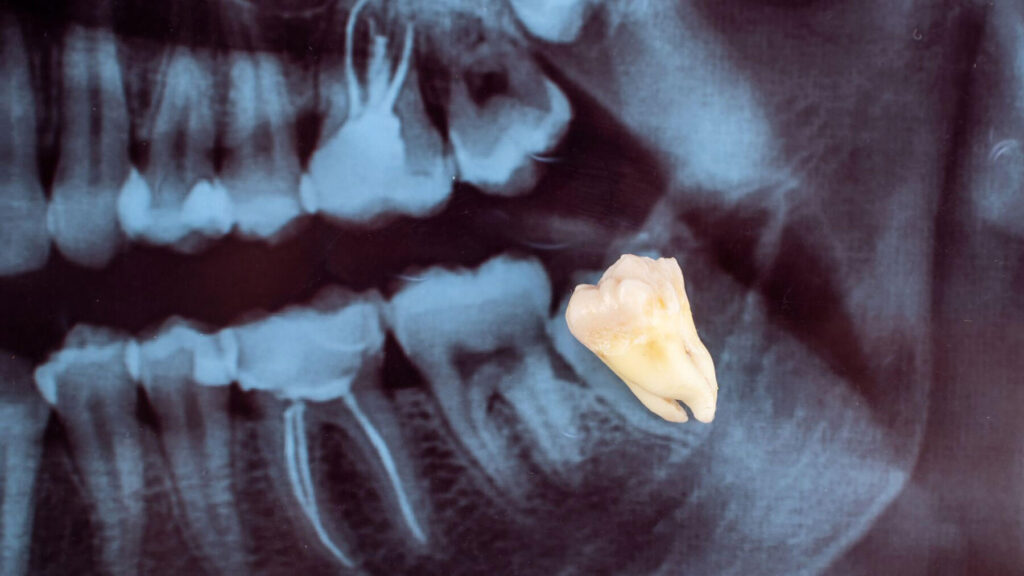

So, while any tooth removal is an “extraction,” whether it’s classified as “surgery” depends on whether incisions, bone removal, or tooth sectioning are necessary. The majority of wisdom tooth removals, especially for impacted teeth, do fall under the category of surgical extractions. Our team at Smiles for Health DDS will always perform a thorough examination, including X-rays, to determine the exact nature of your wisdom teeth and recommend the most appropriate procedure, guiding you every step of the way in your wellness dentistry journey.

Our clinic utilizes advanced imaging, such as panoramic X-rays, to accurately assess the position and root structure of your wisdom teeth. This allows our team at Smiles for Health DDS to determine precisely when a wisdom tooth requires surgical extraction and to plan the safest and most effective procedure for your wellness dentistry needs. If you’re experiencing any issues with your wisdom teeth, contact us for a thorough evaluation.